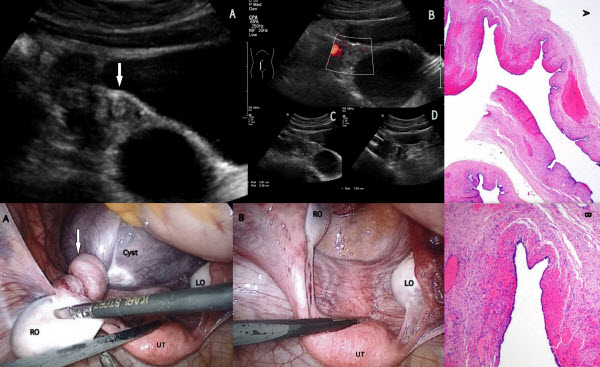

Isolated Fallopian Tube Torsion With Fimbrial Cyst In A 10 Year-old Girl Diagnosed By Ultrasound: A Case Report

Torsion of the fallopian tube without the involvement of the ipsilateral ovary is a rare but important cause of acute abdominal pain in women as it is a surgical emergency. Although uncommon, it should be considered as one of the differential diagnosis in female children presenting with acute lower abdominal or pelvic pain. The diagnosis of isolated fallopian tube torsion is difficult pre-operatively and is often made during laparoscopic or surgical exploration because diagnostic features are usually non-specific. In this report, we present a case of isolated fallopian tube torsion with fimbrial cyst in a young female patient diagnosed pre-operatively by ultrasound.